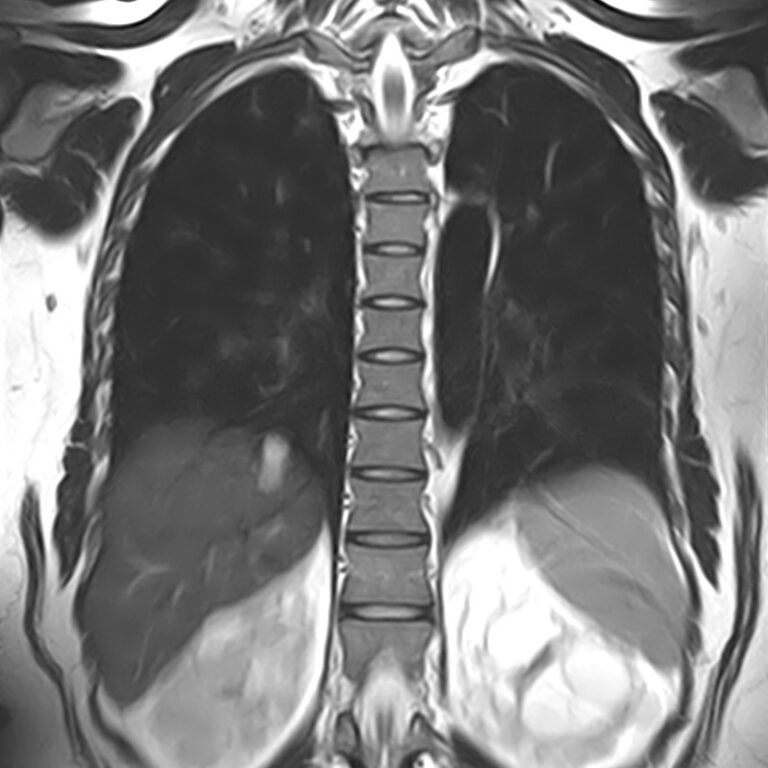

МРТ является современным высокоточным исследованием грудного отдела позвоночника, с помощью которого можно диагностировать различные заболевания, в том числе воспалительные, дегенеративные и опухолевые процессы. Преимуществом данного метода является его безопасность (отсутствие рентгеновского излучения), безболезненность, неинвазивность, при этом высокая информативность.

Клиника «Доступная медицина» оснащена новейшим томографом экспертного класса TOSHIBA VANTAGE TITAN 1,5 Тесла, который позволяет получать превосходные изображения с мельчайшей детализацией всех структур исследуемой области. Это позволяет ставить точный диагноз и выявлять различные заболевания позвоночника на самой ранней стадии.

С помощью МРТ грудного отдела выявляют следующие заболевания позвоночника:

• новообразования;

• степень повреждения спинного мозга в случае переломов тел позвонков;

• грыжи Шморля;

• травматические повреждения тел позвонков и остистых отростков (трещины, переломы, смещения и пр.) — при недоступности КТ;

• разрывы, растяжения связок;

• травмы спинного мозга, нервных корешков;

• протрузии;

• грыжи межпозвонковых дисков;

• остеохондроз позвоночника;

• стеноз спинномозгового канала;

• сосудистые патологии;

• остеомиелит, спондилодисцит;

• рассеянный склероз;

• спондилоартроз;

• спондилез.